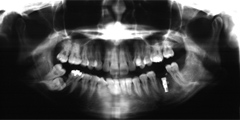

吉本歯科医院では、口内写真とパノラマレントゲンを撮影し、まずは顎の骨の状態まで詳しく確認しました。

(写真(1))虫歯の進行により歯の根っこに膿ができ、歯の周辺の骨まで溶け出している

・虫歯の進行により、歯の根っこに膿ができ、歯の周辺の骨までごっそり溶けてしまい歯がグラグラと揺れだした。

・親知らずを放置していたことにより、健全な歯を横に押し出し全体の噛み合わせ(咬み合わせ)のバランスを崩し、歯並びが悪く、不自然な力で噛み続けていたため歯が揺れだした。